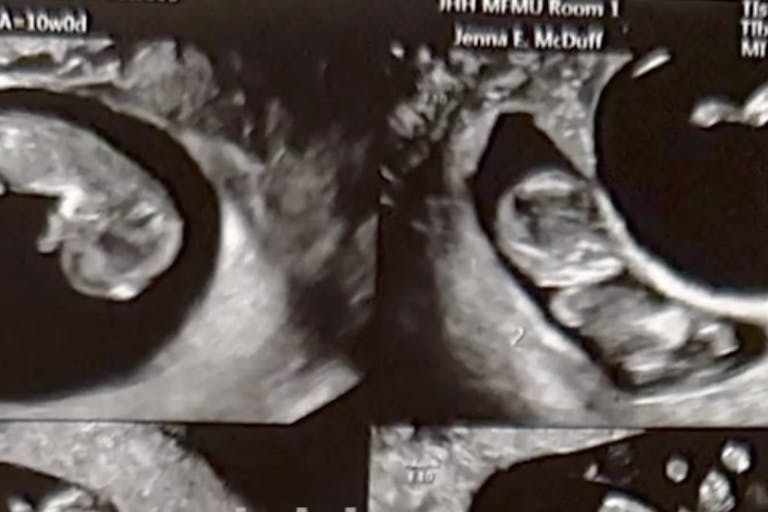

After learning they were pregnant in September of 2023, the couple had their first ultrasound, which initially revealed twins. Then in December, the ultrasound detected two babies in each of the two sacs. Stunned, the couple stared at the screen.

A natural pregnancy of this nature is incredibly rare. Apps told The Mirror, “Our doctor told us that quadruplet pregnancies are around one in 700,000, and being pregnant with two sets of identical twins is even more rare” — about one in 70 million. Hannah Carmack of Alabama was also a mother who experienced one of these extremely rare quadruplet pregnancies, giving birth to two identical sets of twins last year in March— two boys and two girls. All are thriving.